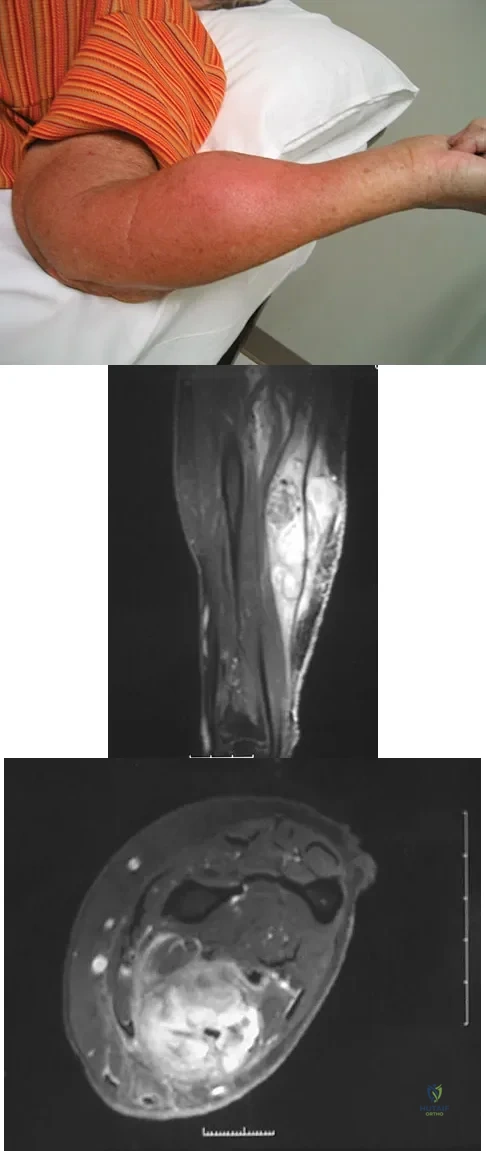

Figure 8a shows the clinical photograph of an 83-year-old woman who has an enlarging left forearm mass. MRI scans are shown in Figures 8b and 8c. What is the next most appropriate step in management?

Explanation